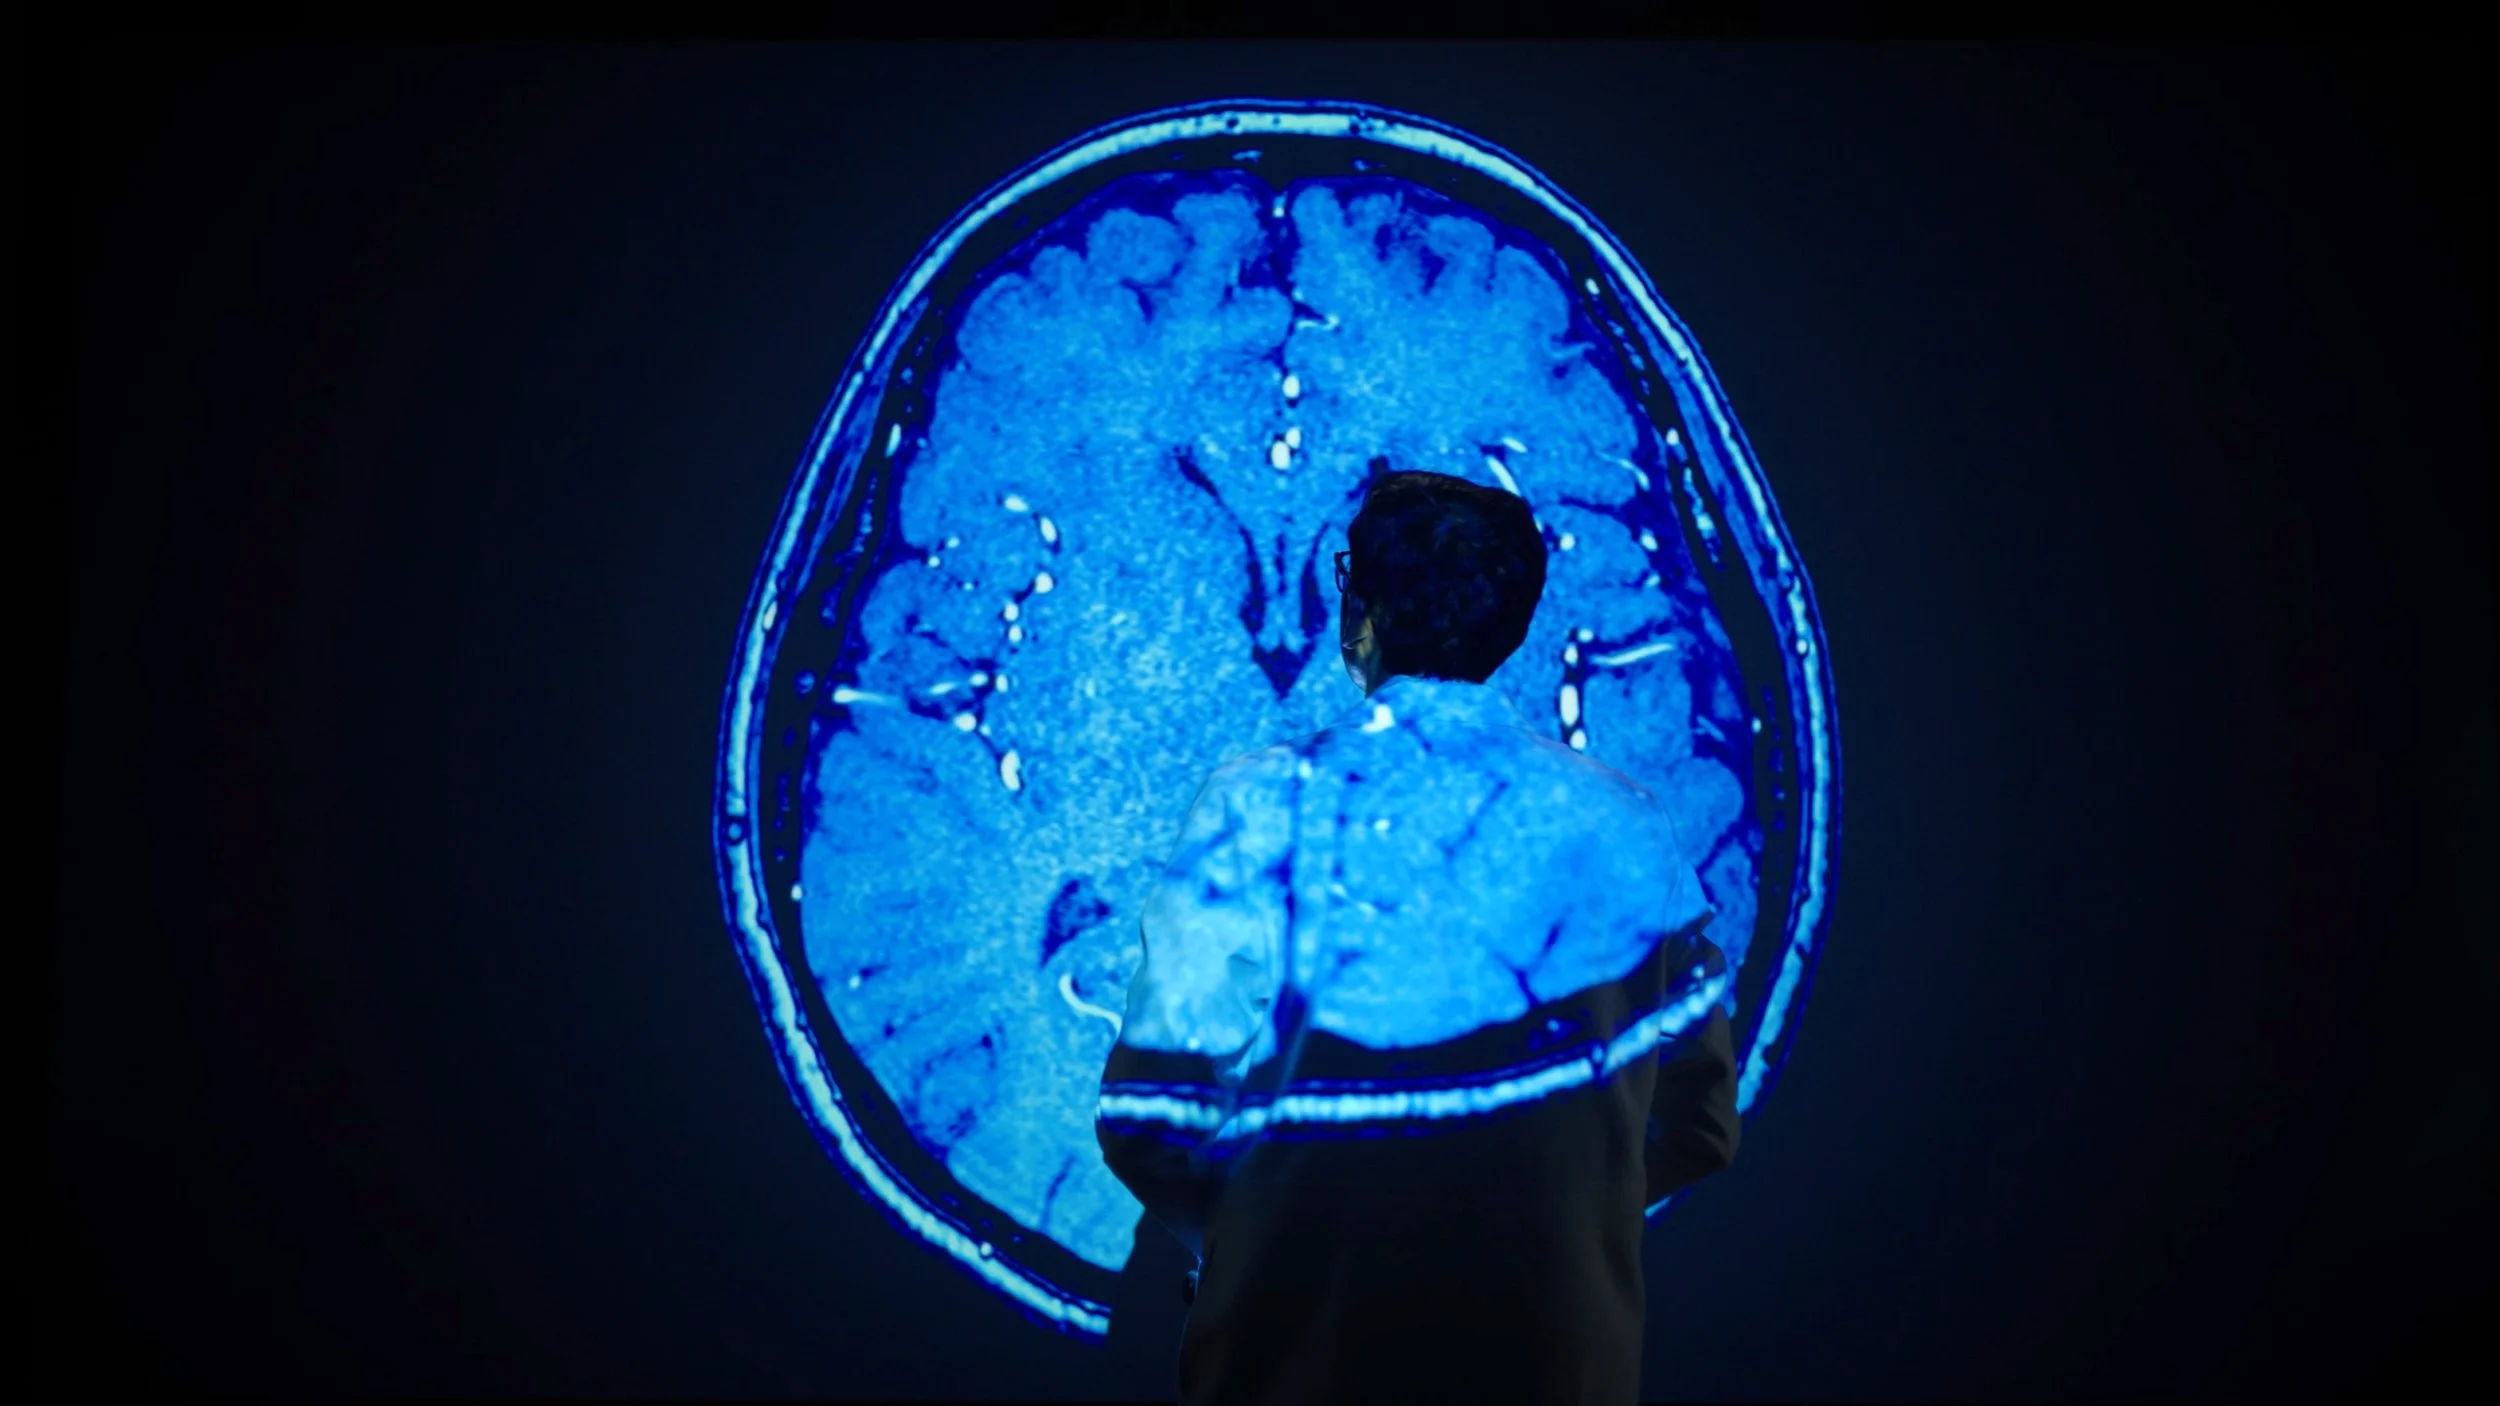

These are the real, everyday heroes. We had the privilege of spending a week capturing real doctors, nurses, scientist, technicians, and staff at work. Day in and day out, they fight to improve and save the lives of every person who walks through their doors. It was a truly humbling and eye-opening experience to be part of this project, and I’m incredibly grateful for the opportunity.